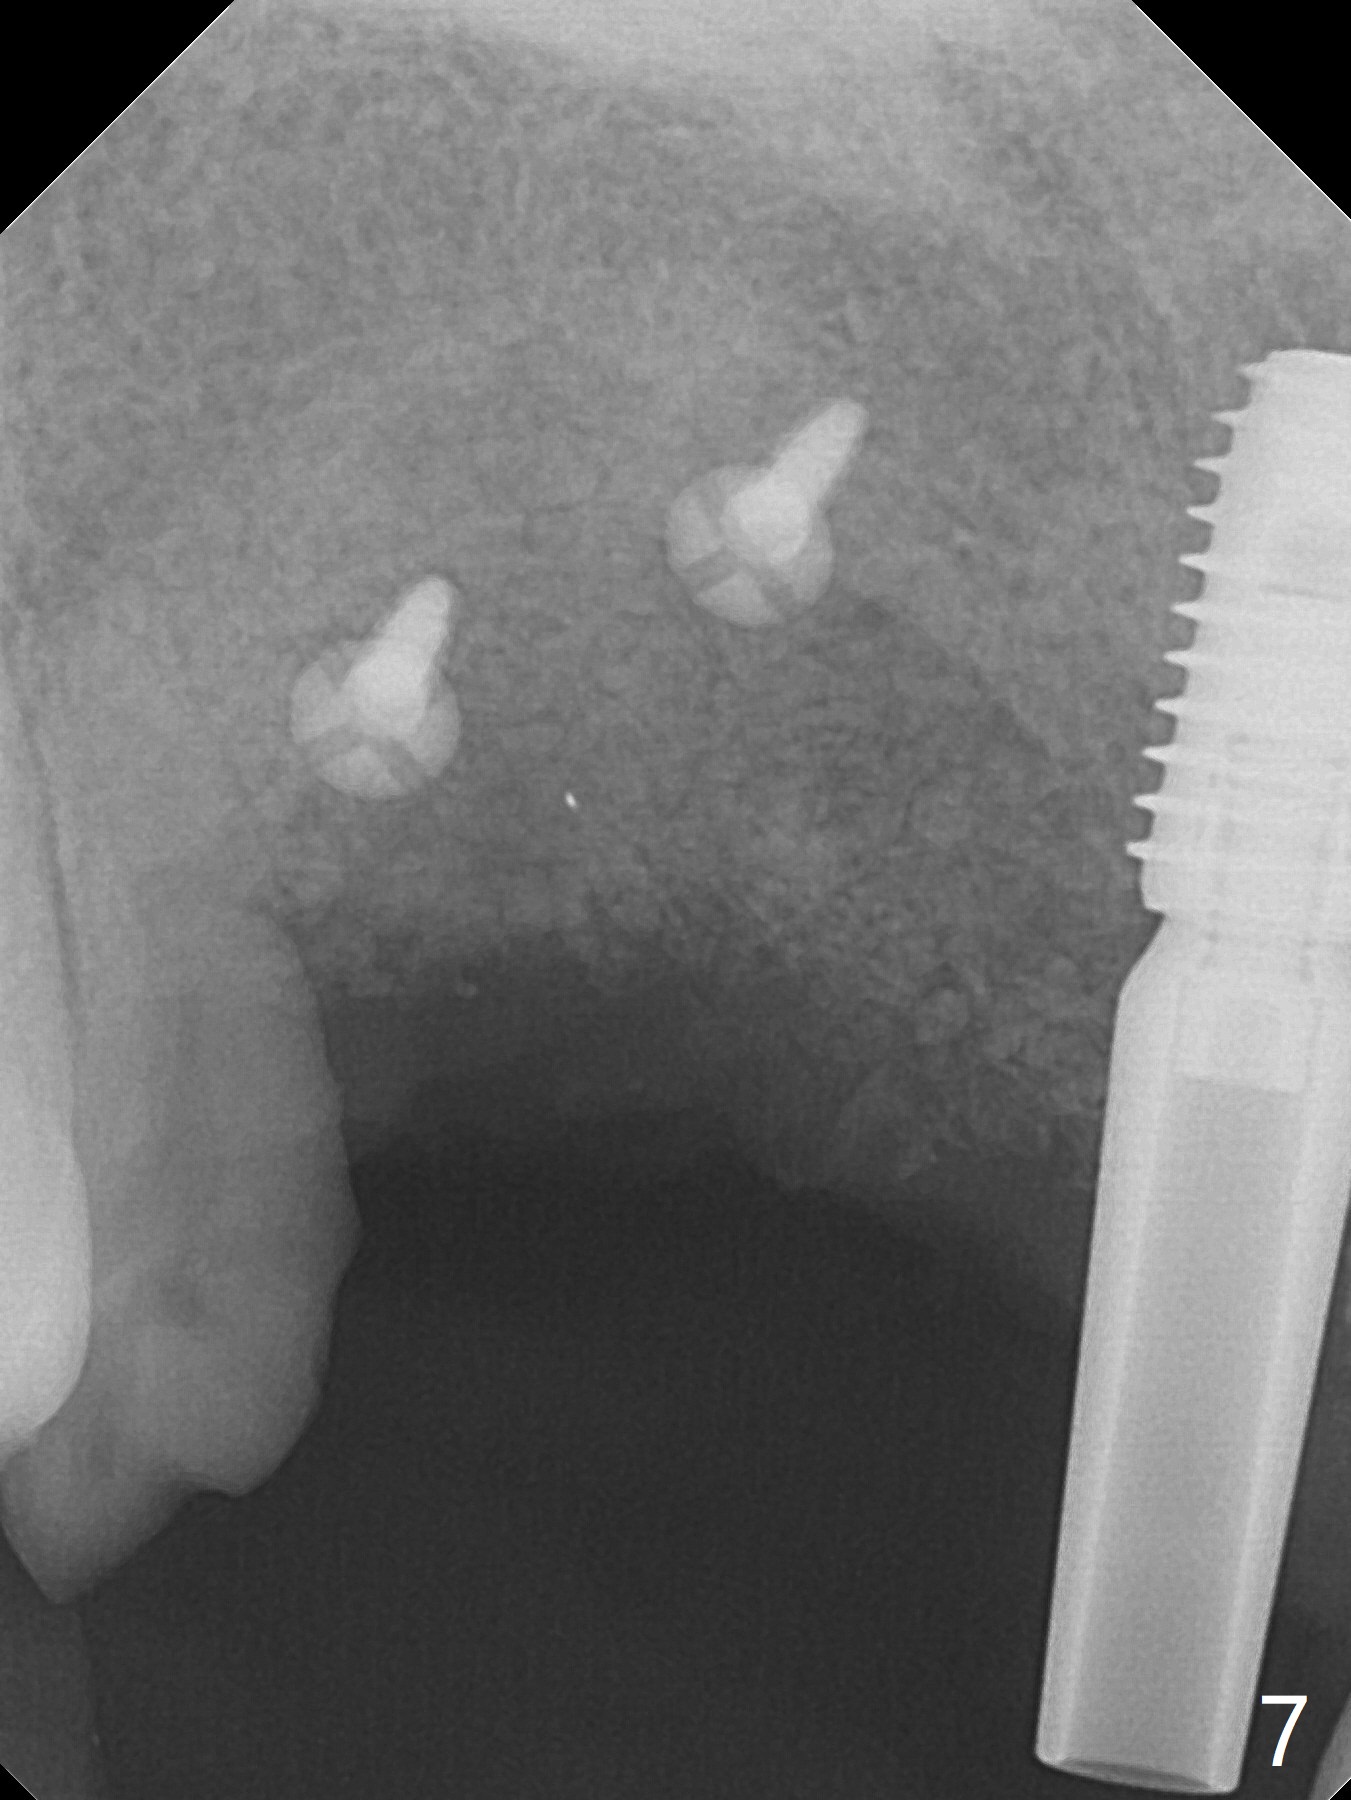

Eleven months post immediate implantation, the implant at #8 (4.5x16 mm, better smaller) is found to have thread exposure buccally (Fig.1) and distally (Fig.2). Immediately post implant removal, a 5x10 mm one is placed equi- or subcrestally distobuccally (Fig.3,4 (to prevent periimplantitis)). It is turned 4 more times later to make sure slightly supracrestally palatally, since the palatal crest is the lowest. After placement of sticky bone palatally, a 4.5(2) mm mill abutment is placed (17 mm long, Fig.5,6). The buccal flap is raised until the anterior nasal (Fig.5 N) foramen. After severing the periosteum and placement of 2 of 8 mm tenting screws (Fig.7), sticky bone (Vanilla allograft/Osteogen; block graft denies) is applied at #6 and 7 sites (Fig.8). Following palatal flap separation, the wound is closed in an apparent tension free manner (Fig.9). Periodontal dressing is applied. After wound healing, lab-fabricated provisional is delivered.